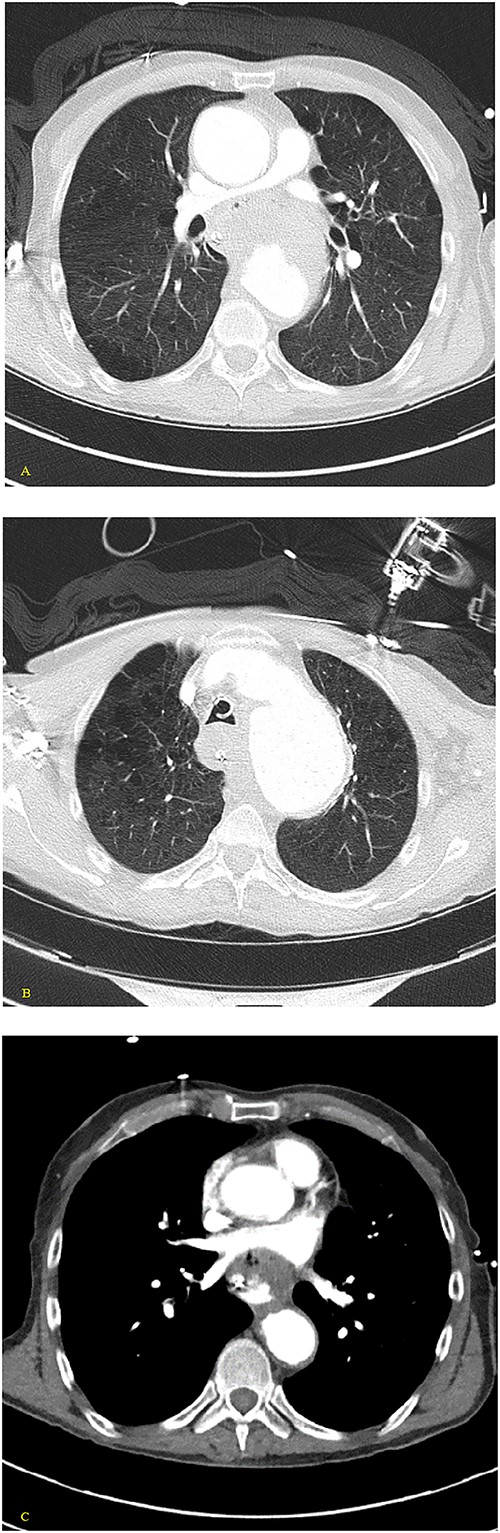

(A, B) Axial nonenhanced CT chest with contrast and (C) axial enhanced CT chest with contrast reveal an extensive clot around the aorta and around the esophagus with some mass effect on the pulmonary arteries and the LA. Clot fills the aorta.